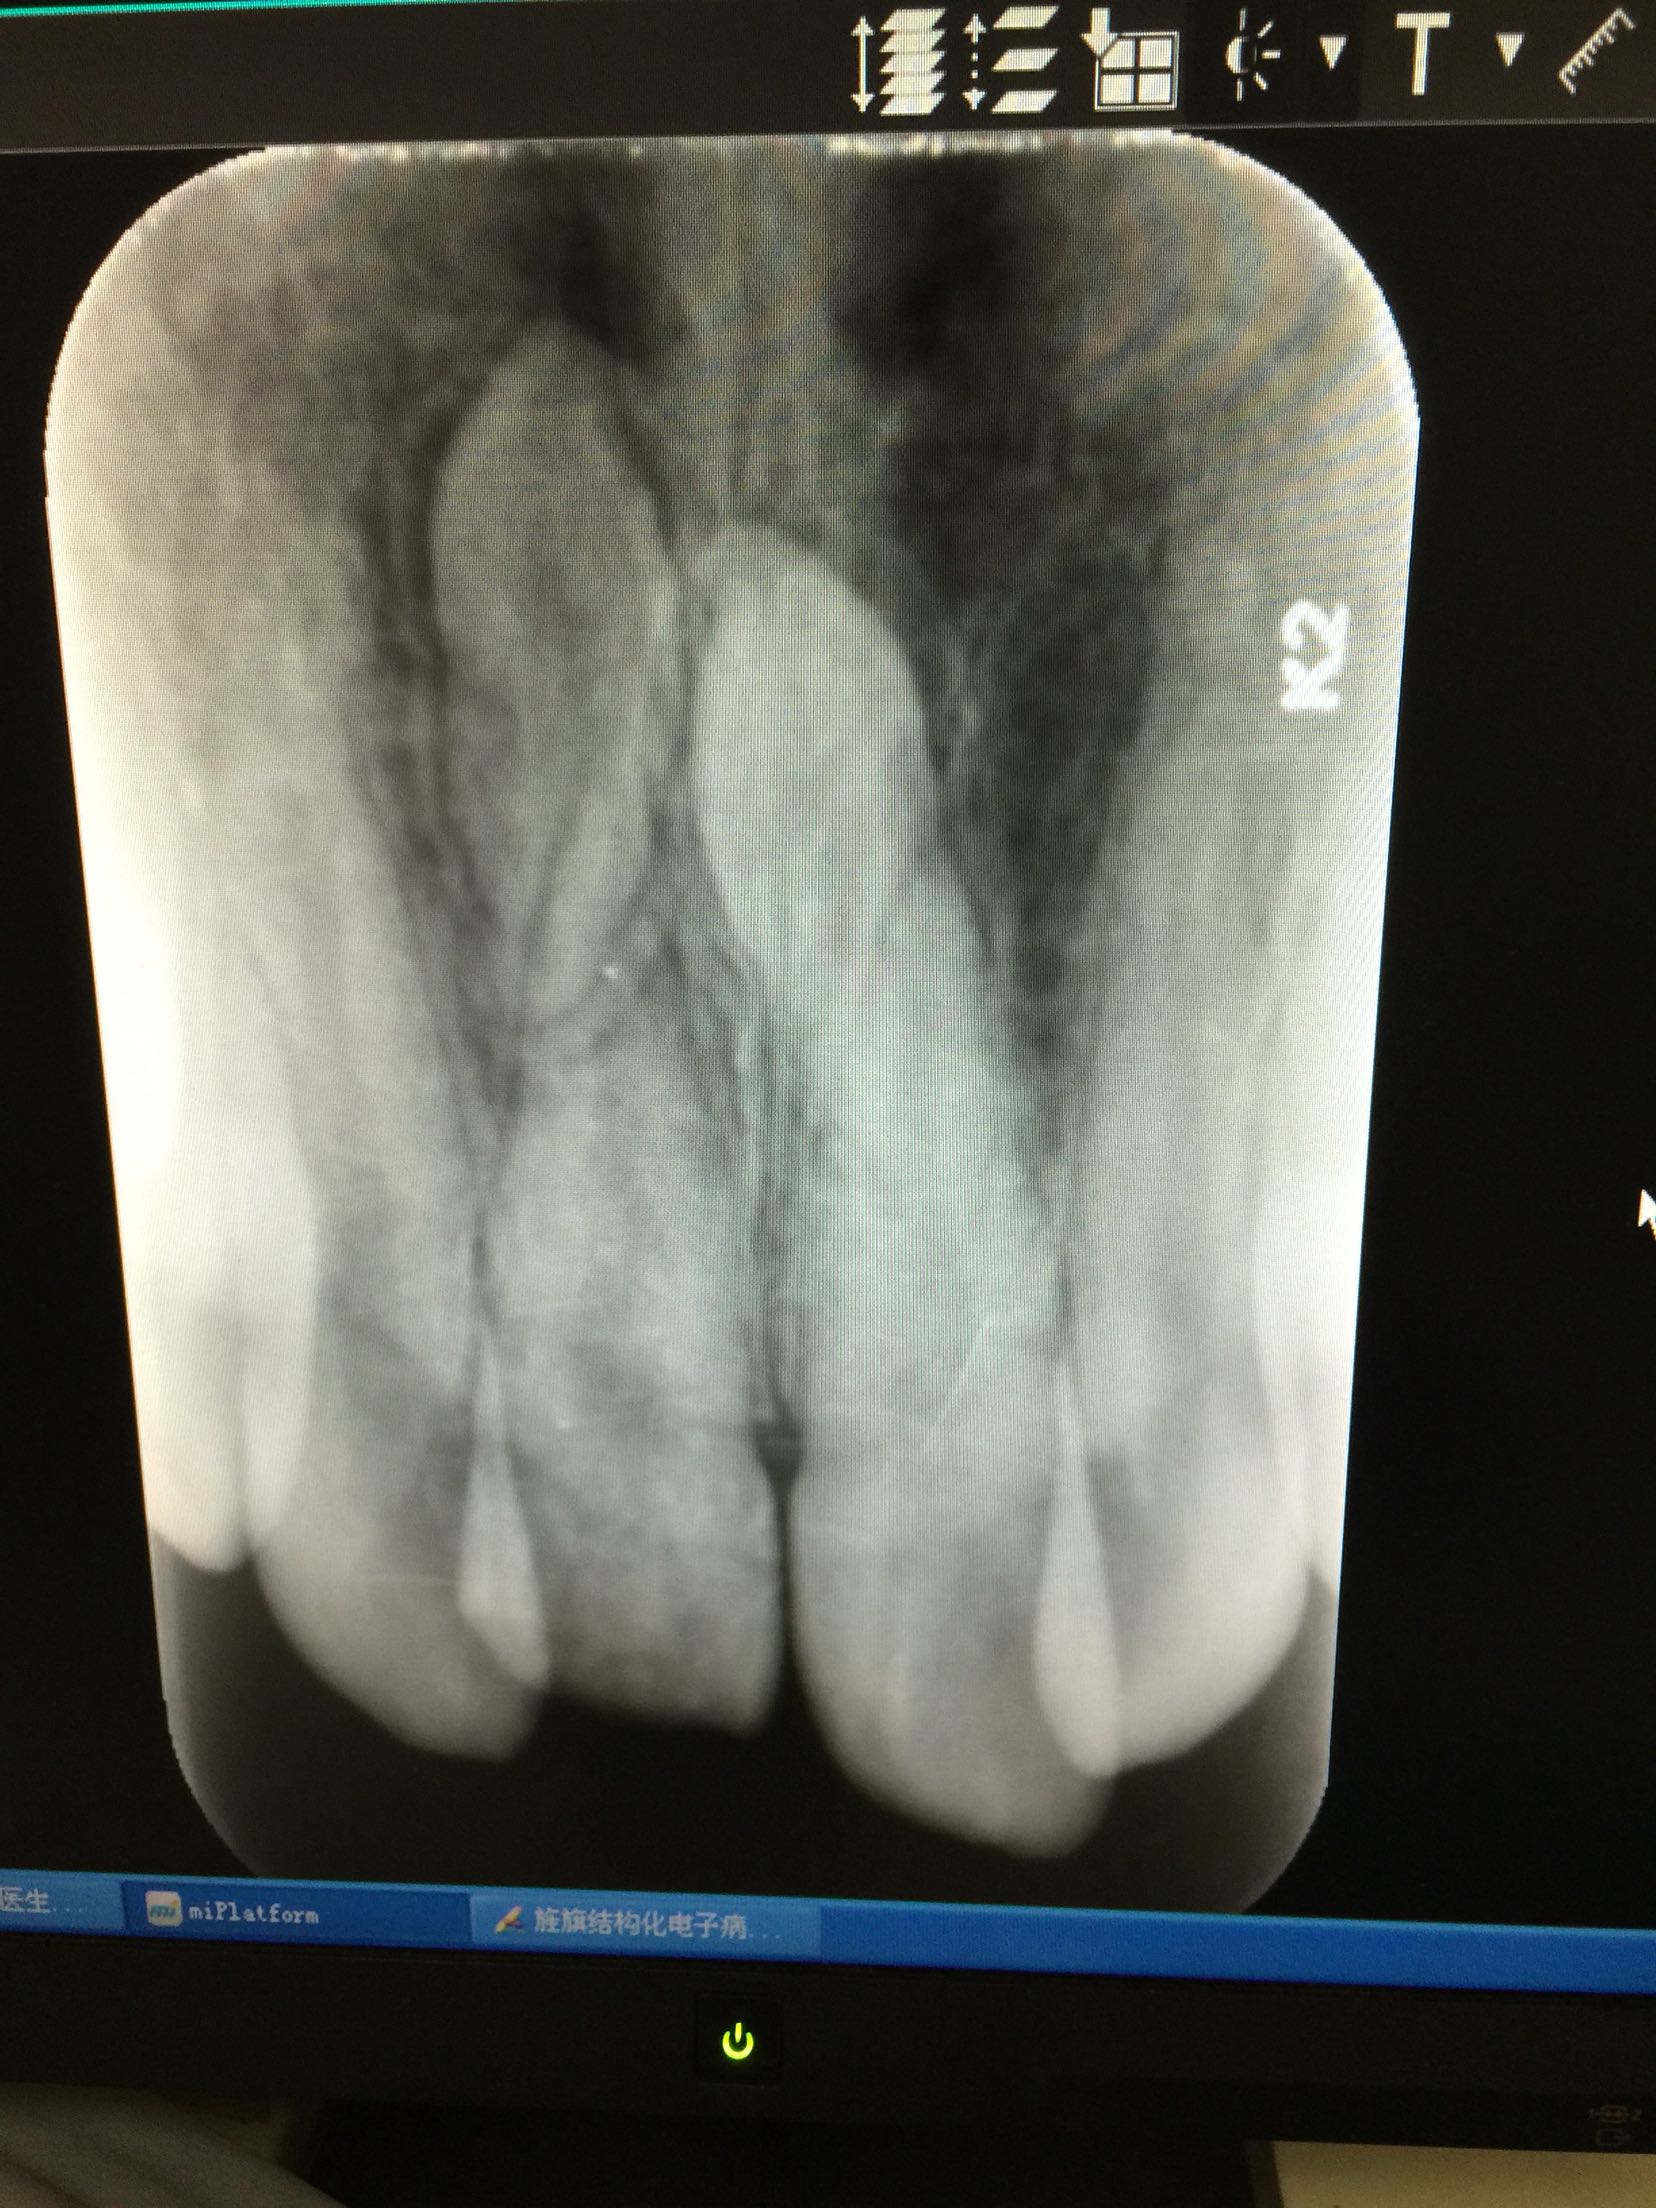

检查:全口卫生好,牙龈正常无退缩。11牙牙冠釉质牙本质折断,累及整个切缘,仅余留颈1/3,断面位于龈上4mm,可见白色暂补料,牙齿颜色正常,叩痛+,冷+,不松,牙髓电活力测试无反应,咬合关系正常。 RVG示:11牙牙冠部分缺损,已累及髓腔,未行根管治疗,很尖区未见异常,11、21牙根尖可见两颗多生牙。